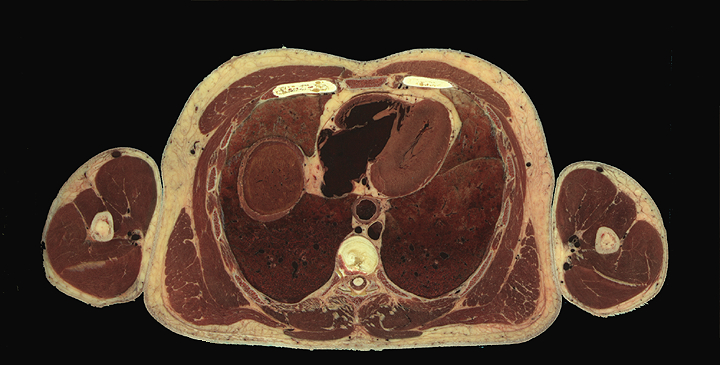

Full torso, unlabelled

Thorax structures, high resolution